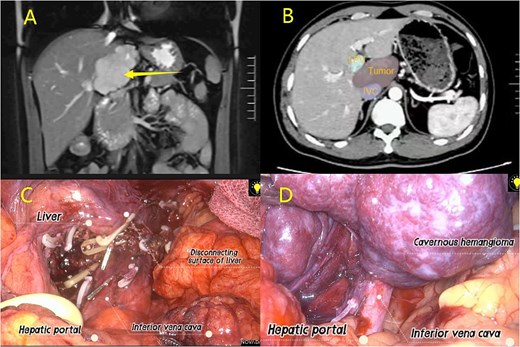

(A) MRI examination; (B) CT examination; (C–D) Laparoscopic resection of caudate lobe hemangioma procedure.

IVC and tumour exposure

After hepatic portal blockage, dissecting tissues from the right hepatic hilum posteriorly exposed the IVC. The short hepatic veins between the IVC and caudate lobe were carefully isolated and secured with hemolocks and titanium clips. The left hepatic lobe was mobilized, the Arantius ligament dissected, G1L1 clamped with the same clips, and dissection finalized via ultrasonic scalpel. Cholecystectomy was additionally performed to enhance surgical visualization (Fig. 2; Video S1).

Hepatic caudate lobe parenchymal resection

Guided by the IVC during hepatic parenchymal resection (especially with hepatic hilar occlusion), dissection began at the right hepatic hilum. An ultrasonic scalpel incised the liver along the hemangioma margin, following the IVC until the incision was perpendicular to it. The hemangioma was retracted left to fully expose short hepatic vessels between the caudate lobe and IVC; these vessels were carefully dissected, clamped, and transected. The ultrasonic scalpel continued to resect liver tissue until the lesion was fully freed. Bipolar electrocoagulation achieved hemostasis post-specimen removal, and a drainage tube was placed and secured in the surgical field (Fig. 2).